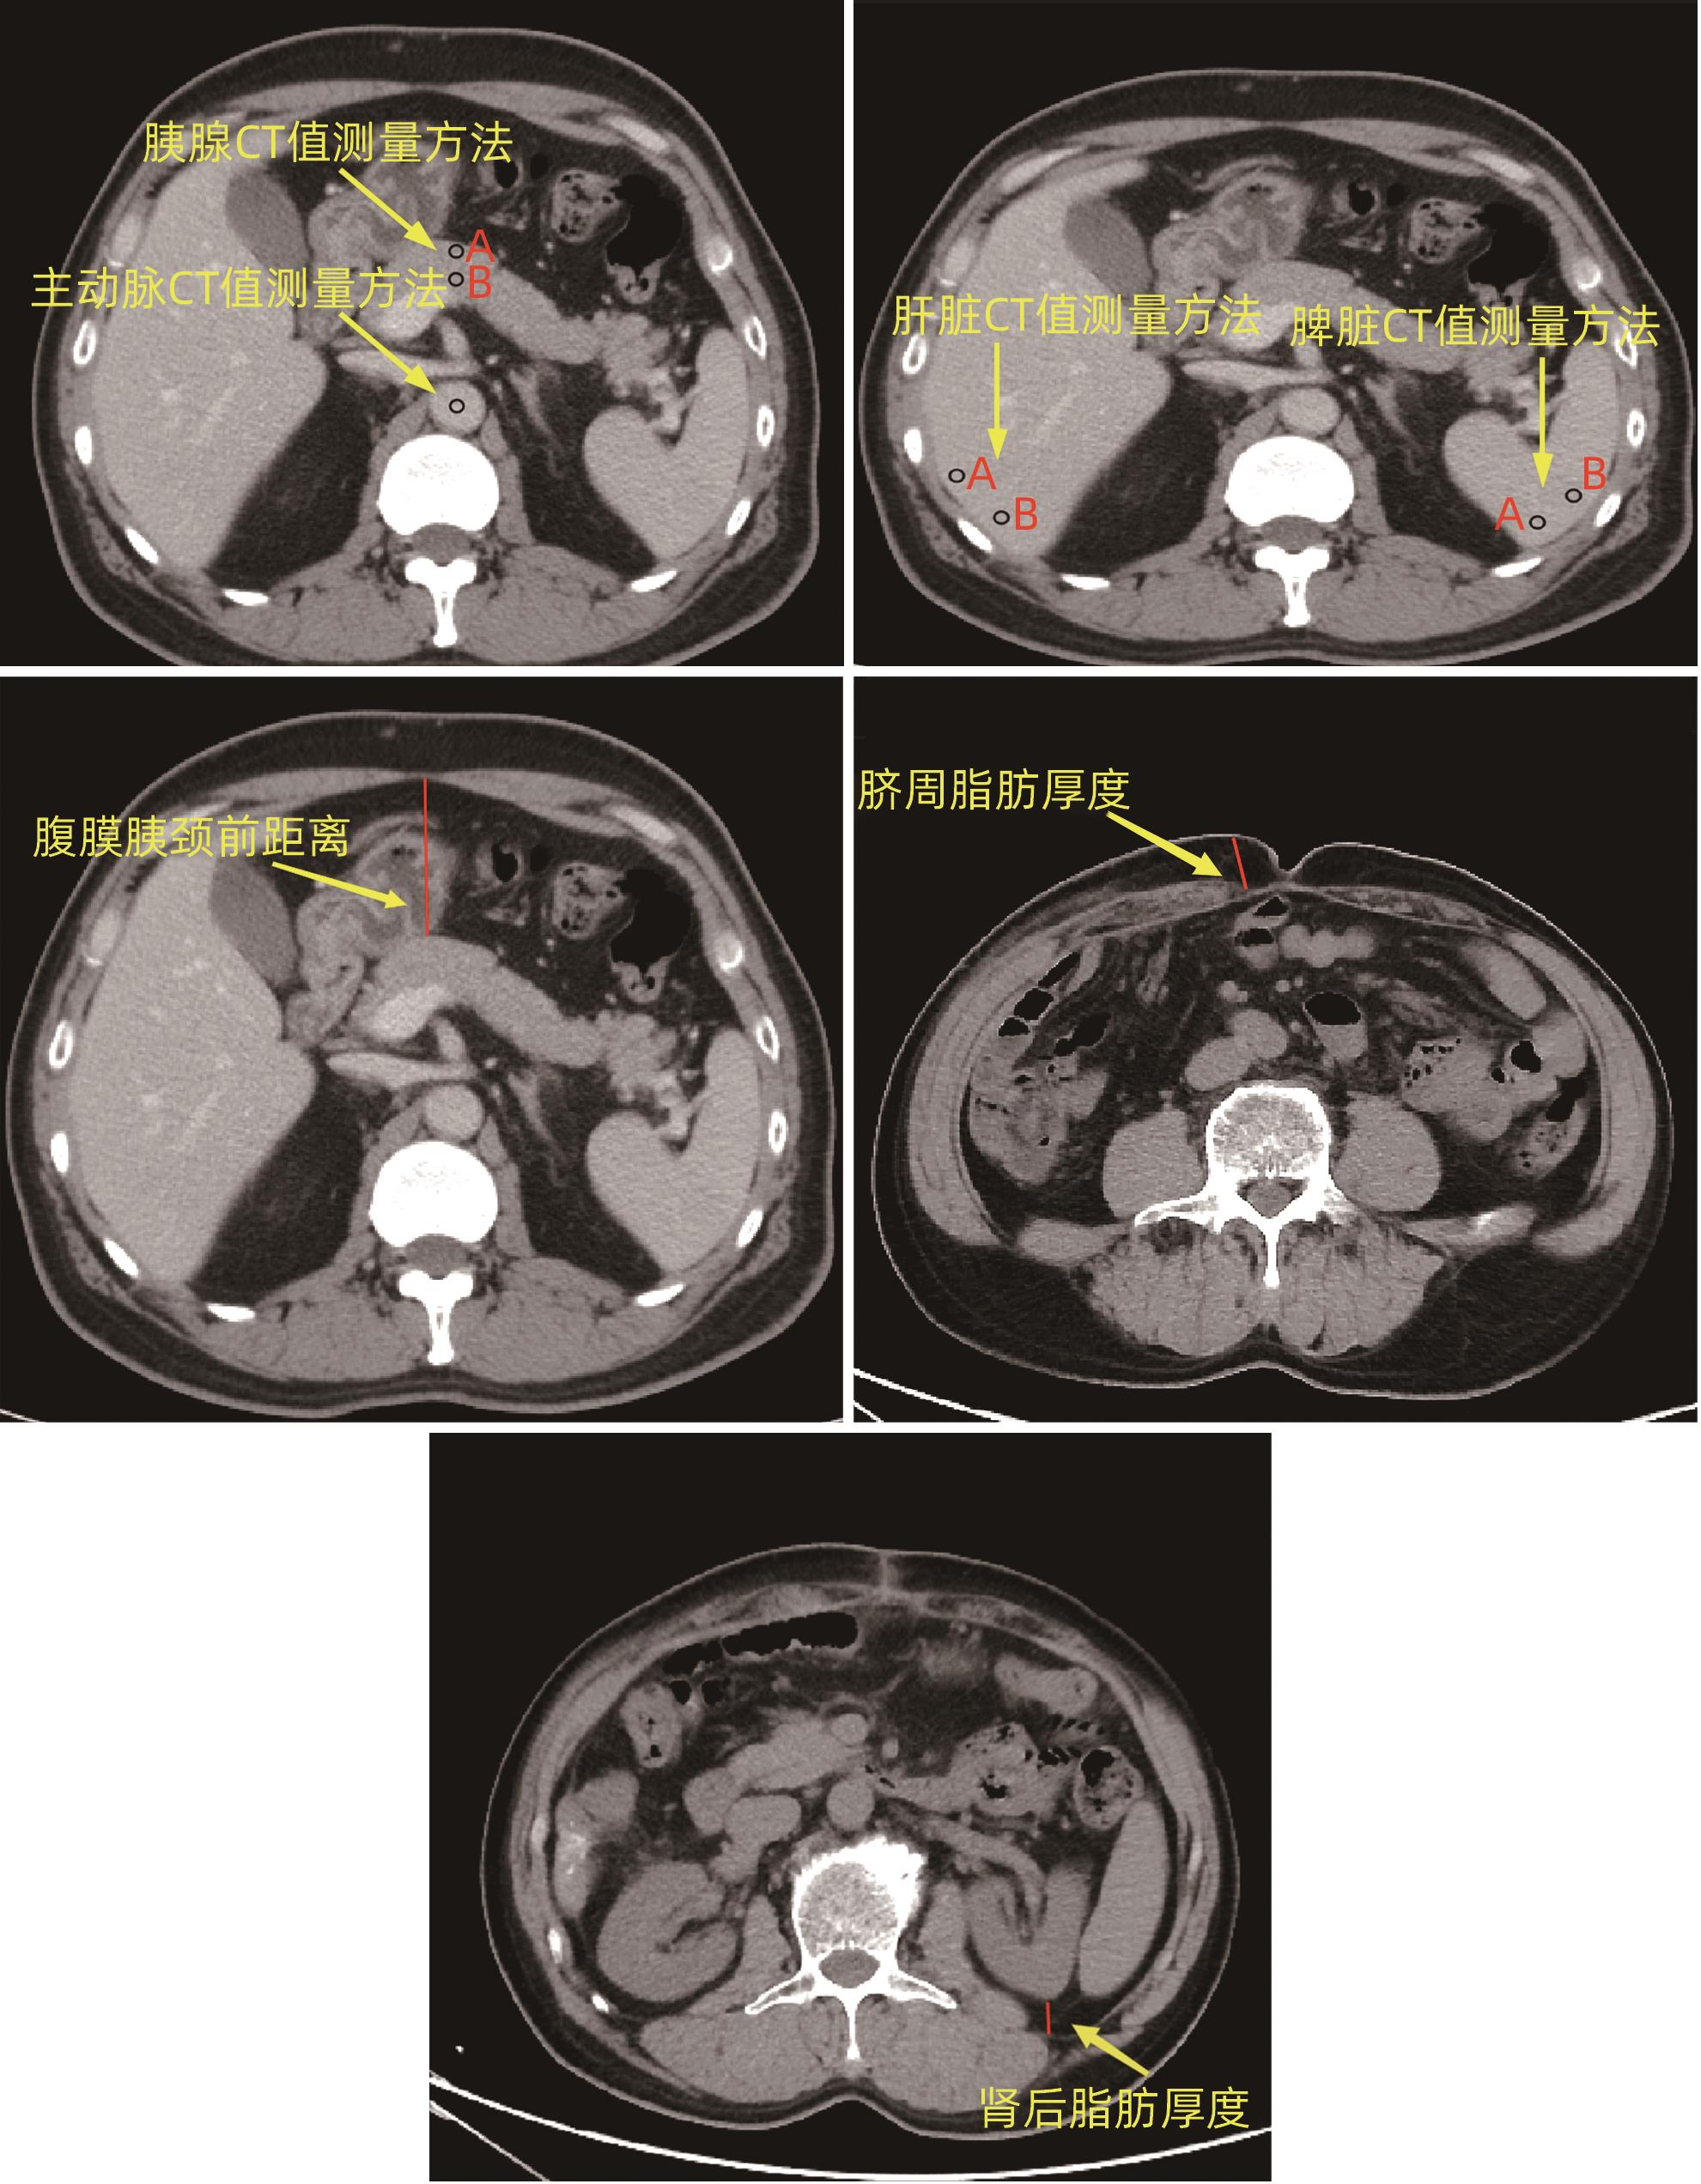

术前ALT/AST联合多期CT影像学指标对胰十二指肠切除术后临床相关胰瘘的预测价值

潘均昊, 辛建, 王春晖

2024, 40(9): 1859-1867. DOI: 10.12449/JCH240922

摘要(834) HTML (359) PDF (2208KB)(47)

摘要:

目的  探讨胰十二指肠切除术后发生临床相关胰瘘(CR-POPF)的危险因素,并建立预测模型,对CR-POPF患者进行早期预测。  方法  选取北部战区总医院2019年1月—2023年10月244例行胰十二指肠切除术的患者,经过严格的纳入排除标准筛选后最终纳入179例患者,根据是否发生CR-POPF分为非CR-POPF组(n=120)和CR-POPF组(n=59)。采用单因素和多因素Logistic回归分析确定CR-POPF相关的独立危险因素,并构建列线图。采用受试者工作特征曲线评价预测效果,校准曲线评价模型校准度,用临床决策曲线和临床影响曲线分析验证模型的临床应用价值。计数资料组间比较采用χ2检验或Fisher精确概率法;计量资料符合正态分布的2组间比较采用成组t检验,偏态分布的2组间比较采用Mann-Whitney U检验。  结果  179例患者中59例发生CR-POPF,发生率为33.0%。经过多因素Logistic分析确定术后CR-POPF的独立危险因素:较大的ALT/AST(OR=2.221,P=0.004)、主胰管直径≤3 mm(OR=0.276,P=0.022)、较大的腹膜胰颈前距离(OR=1.034,P=0.027)、较小的细胞外体积分数(OR=0.001,P=0.005)。根据上述4个独立危险因素构建预测胰十二指肠术后CR-POPF的列线图,该模型的受试者工作特征曲线下面积为0.837,敏感度为0.932,特异度为0.725。决策曲线和影响曲线的结果也显示该列线图具有良好的临床实用性。  结论  术前临床指标联合多期CT共同预测胰十二指肠切除术后CR-POPF的模型效能良好,可以在术前对胰瘘高危患者进行早期识别,进一步指导临床工作。